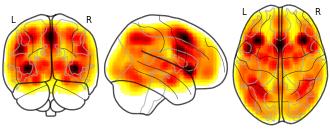

PD MKDAChi2 Meta Analysis: included : 2024-07-06 21:37:52

License information was derived automaticallyDescriptionA collection of 13 brain maps. Each brain map is a 3D array of values representing properties of the brain at different locations.

MKDAChi2 meta analysis with FDRCorrector

PD MKDAChi2 Meta Analysis: included : 2024-07-06 21:37:52:...

License information was derived automaticallyDescriptionCollection description

MKDAChi2 meta analysis with FDRCorrector

Subject species

homo sapiens

Modality

Other

Analysis level

meta-analysis

Map type

P